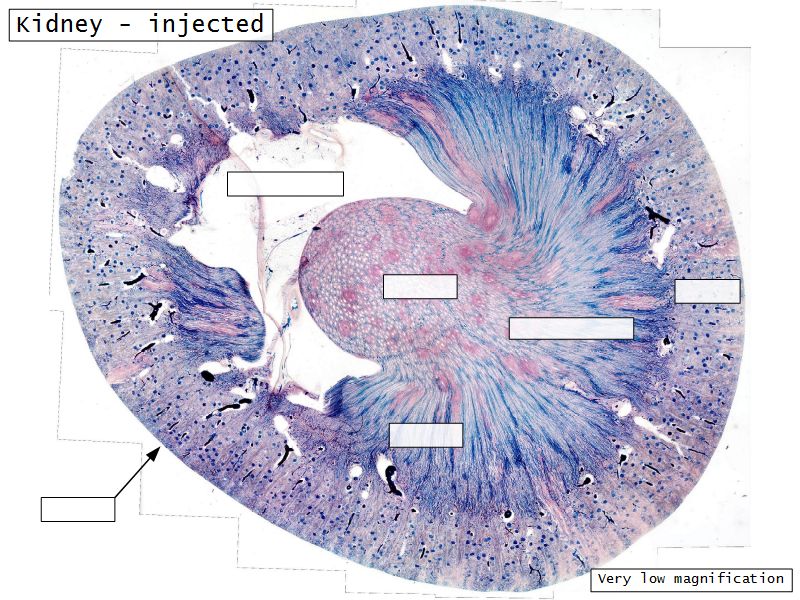

Kidney

- Capsule

- Cortex

- Medulla

- Multilobar

Multilobar

- Conical mass (pyramid)

- Medullary tissue

- capped with

- Cortex

- Delineated by

- Renal columns

- Apex of pyramid

- Papilla

- Projects into renal pelvis

- Make an annotated drawing of the macroscopic view of the kidney.